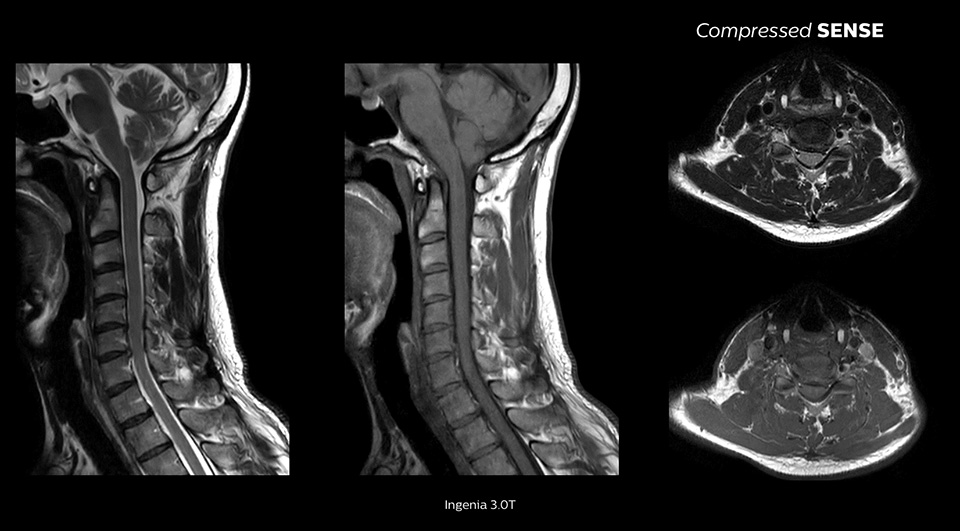

Utilizzando Compressed SENSE, in pratica senza dover modificare i nostri protocolli standard, abbiamo ridotto i tempi di scansione del 20%. Nessuno dei medici sa distinguere l'esito di una scansione eseguita con Compressed SENSE da quello di una scansione eseguita con mezzi convenzionali."

Consente un miglioramento della risoluzione spaziale fino al 64%1